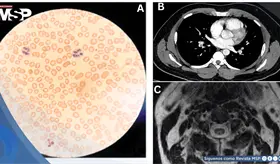

Un reciente estudio ha revelado que las características vasculares de la retina, que se pueden observar mediante fotografía de fondo ocular, están estrechamente asociadas con el riesgo de sufrir un accidente cerebrovascular.